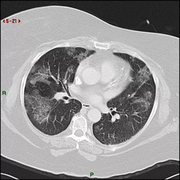

胸片怎么看

学会看胸片是临床医生必备的技能之一,首先,看胸壁的X线表现,观察胸壁软组织有大的肿块,有皮下积液、积气,同时观察肋骨的连续性是否有中断,这是肋骨骨折的X线征象...73227人收听

在临床上胸部X光片检查是常用的一种检查方法,它是利用X线产生图像,从而观察胸部的病变。胸片的观察需要按一定的顺序,一般可以按照从上往下的顺序,观察双肺上叶...1人收听